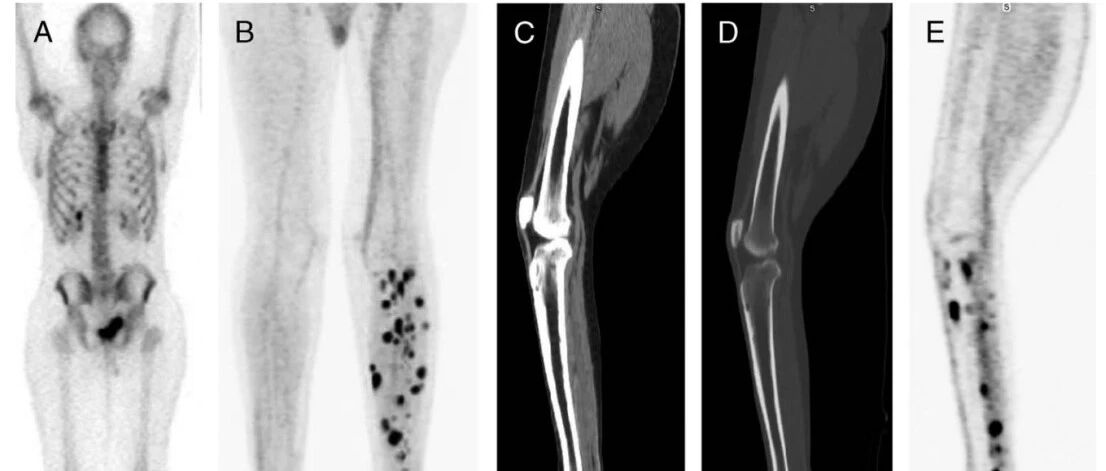

这种罕见病名字里没有“骨”,却专挑骨头下手?PET让它无处躲藏